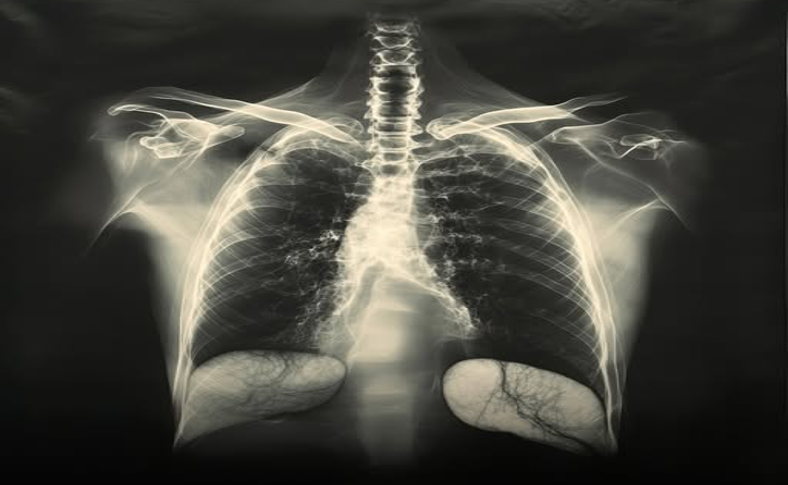

জীববিজ্ঞানে যুগান্তকারী এক আবিষ্কারে যুক্তরাষ্ট্রের ক্যালিফোর্নিয়া বিশ্ববিদ্যালয়ের (ইউসিএসএফ) গবেষকরা ফুসফুসের এক নতুন ও বিস্ময়কর ভূমিকা চিহ্নিত করেছেন। ২০১৭ সালের ২২ মার্চ নেচার সাময়িকীতে প্রকাশিত গবেষণায় তারা জানান, ইঁদুরের দেহে প্লেটলেট তৈরির প্রধান স্থান হিসেবে কাজ করছে ফুসফুস—যা এতদিন পর্যন্ত শুধু শ্বাসপ্রশ্বাসের অঙ্গ বলেই বিবেচিত ছিল।

এই গবেষণায় দেখা গেছে, একটি ইঁদুরের ফুসফুস প্রতি ঘণ্টায় ১ কোটির বেশি প্লেটলেট তৈরি করছে। এই সংখ্যা মোট দেহের প্রয়োজনীয় প্লেটলেটের অর্ধেকেরও বেশি। এতদিন চিকিৎসাবিজ্ঞানীদের ধারণা ছিল, এসব রক্তকণিকা তৈরি হয় মূলত অস্থিমজ্জায়। কিন্তু নতুন এই গবেষণা সেই প্রচলিত ধারণাকে চ্যালেঞ্জ ছুঁড়ে দিয়েছে।

দুই-ফোটন ইন্ট্রাভাইভাল ইমেজিং নামে একটি উন্নত প্রযুক্তির সাহায্যে জীবিত ইঁদুরের ফুসফুসে রক্তকণিকার আচরণ পর্যবেক্ষণ করেন গবেষকরা। এই ইমেজিংয়ের সময় তাঁরা দেখেন, ফুসফুসের ভেতর রক্তনালিতে বিস্তর মেগাকারিওসাইট (প্লেটলেট উৎপাদক কোষ) অবস্থান করছে, যাদের ভূমিকা এতদিন তেমন গুরুত্ব পায়নি।